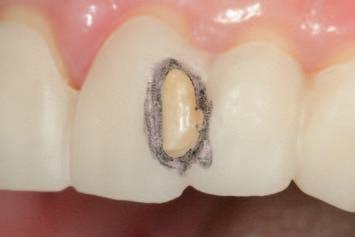

n Before initiating tooth preparation with diamond burs under copious water coolant, highly visible contrasting marks should be applied to the window perimeter of the preparation guide adjacent to the identified areas of

interference (Figure 3). These visual cues enhance intra-operative visibility and reduce the risk of over-preparation, which can occur when the guide’s reference contours are obscured by the coolant spray.

n Tooth structure is reduced until it conforms precisely to the contours of the preparation guide. The removal of the contrasting marker ink, caused by direct contact with the rotating diamond bur, indicates that the target reduction depth has been achieved. This visual endpoint ensures accurate, conservative preparation aligned with the contours of the planned definitive

(

restoration

Figure 4).

FIGURE 3: Pre-operative marking of the preparation guide with a visually contrasting colour prior to tooth reduction.

A C B

FIGURE 4: The appearance of the guide following the tooth reduction procedure. The clinician should stop the procedure the moment the contrasting ink has been displaced.

FIGURE 5: Evaluation of the clinical situation before and after the planned tooth reduction, highlighting the subtle and conservative but clinically meaningful changes that have been made, prior to tooth preparations for indirect restorations.

n Upon removal of the tooth reduction guide, a subtle, conservative but clinically meaningful elimination of anticipated interferences may be confirmed (Figure 5). The guided reduction procedure has simplified the subsequent process of tooth preparation for indirect restorations, at the next step of the treatment plan.

n Subsequent conventional tooth preparations can now be implemented as minimally as possible, as interferences have been eliminated with control and precision.